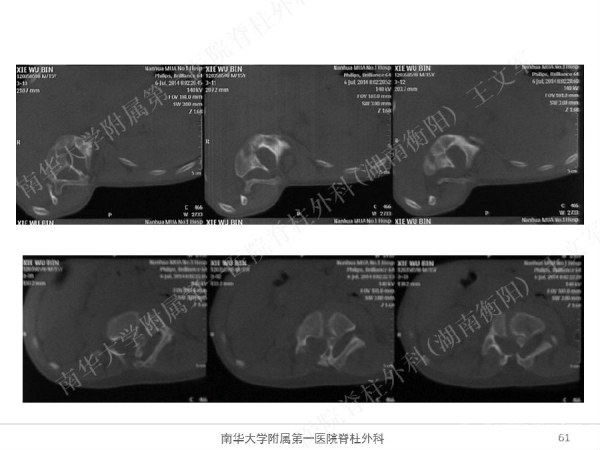

拥有完全自主知识产权的滑槽钉生长棒非融合技术,由南华大学附属第一医院脊柱外科王文军教授研发。

该技术在提供良好矫形固定效果的同时,保留了脊柱生长潜能、尽可能减少对患儿脊柱生长的影响,初步临床效果显示该系统是简单安全有效的,是严重儿童早发脊柱侧弯矫形治疗的一种有益尝试。

擅长脊柱脊髓疾病的微创及非融合手术治疗,目前率领科室开展的先进微创手术有:椎间孔镜技术、经皮穿刺腰椎外固定支架术治疗胸腰椎骨折、腹腔镜下人工腰椎间盘置换术、胸腔镜下胸椎前路手术、腰骶椎轴向融合术。率先在全国业界提出组合微创技术的理念,大大提升了脊柱微创技术的应用范围和治疗效果。拥有自主知识产权的生长棒技术在早发性脊柱侧弯术中的应用解决了儿童脊柱侧弯既早期矫形,又不影响生长发育的世界性难题。